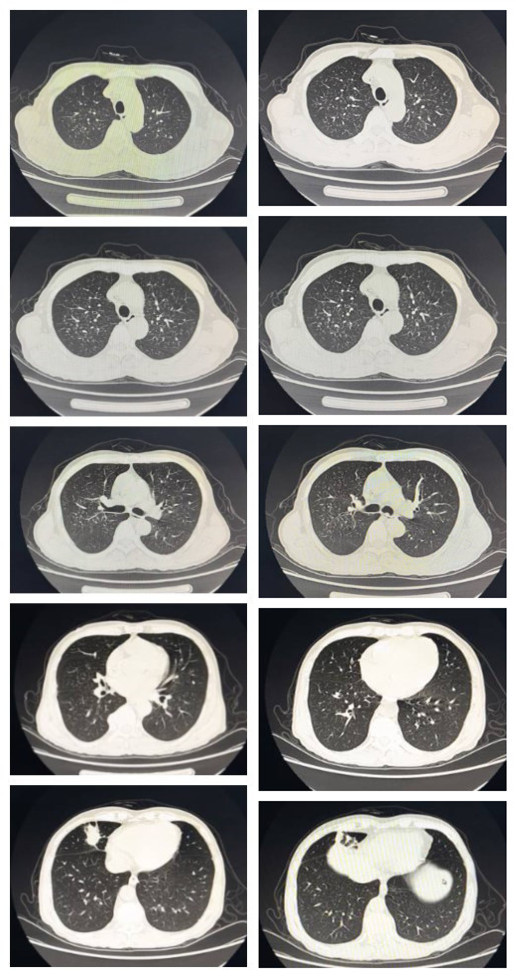

双肺弥漫性磨玻璃密度影这个典型病例请收好

影像所见: 双肺纹理增粗,模糊,双肺见弥漫性斑点状阴影;中肺野见小团

两肺多发斑片影,胸膜下分布

双肺纹理弥漫性增粗,可见多发大小 均匀的小斑片影